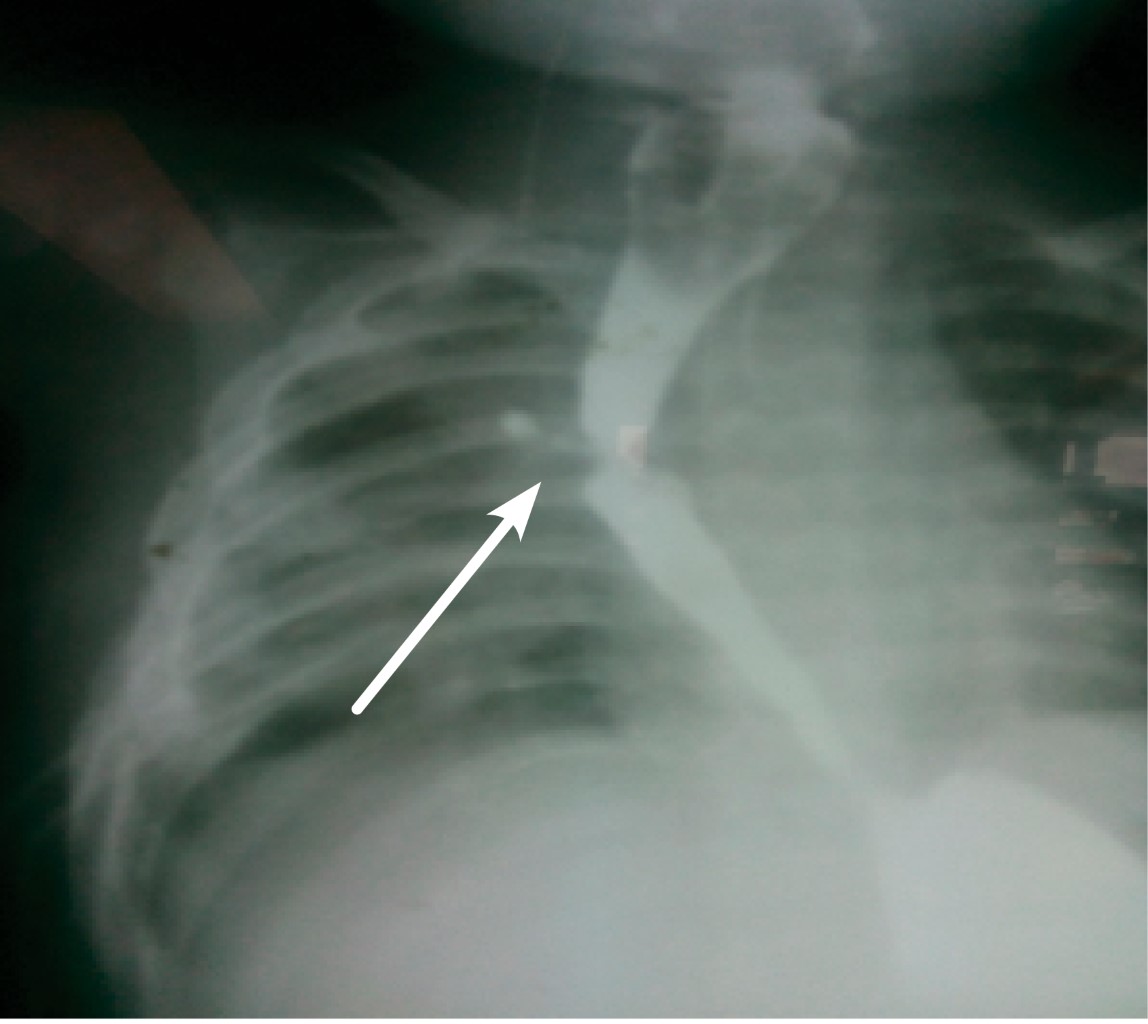

En la AE el tubo no progresa más de 10 cm de la comisura labial, se debe confirmar radiográficamente, lo cual, junto con una broncoscopia, nos ayudará a clasificar el tipo de malformación a tratar (Figura 1). Los pacientes con atresia esofágica tipo I tienen un cuadro clínico similar a los otros tipos de atresias, a excepción de que no presentan gas a nivel intestinal en la radiografía.5-7 Previo al manejo quirúrgico se debe realizar un ecocardiograma, con el objetivo de descartar anomalías asociadas y establecer la posición del arco aórtico, esto es indispensable para definir el sitio de la toracotomía.

Radiográficamente: con silueta cardiaca dentro de la normalidad y radiopacidad abdominal total (ausencia de gas intestinal). Se realizó valoración cardiológica y se encontró ducto arterioso sin repercusión hemodinámica y arco aórtico a la izquierda. La broncoscopia (Storz rígido 3.0 d.i.) muestra ausencia de fístula traqueoesofágica, con lo que se diagnostica AE tipo I y se clasifica, según Okamoto, en clase I, por anomalía cardiaca menor y peso al nacer mayor de 2 kg, con una supervivencia esperada de 100%.

Figura 1